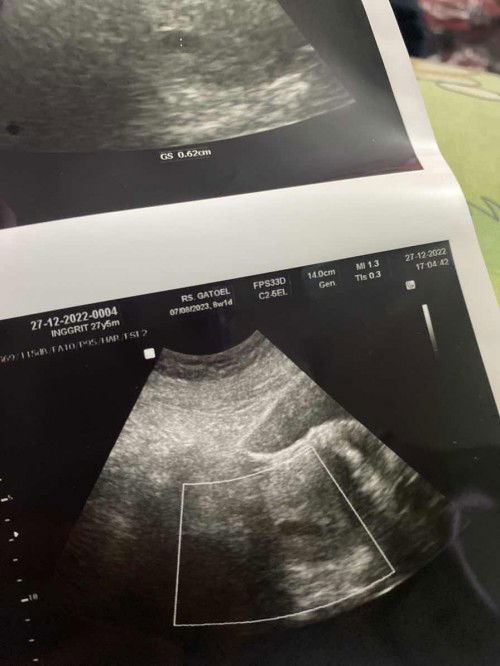

Beda hasil USG

Halo bunda, saya mau sdikit crta dan bertanya. Jd, saya prnah keguguran di bln januari th ini. Kmudian saya memutuskan untuk promil ke dokter di bulan juni kmrn. Alhmdulilah skg saya sudah positif hamil jalan 8w. Kebetulan td pagi saya kontrol ke klinik tmpat saya promil dan dilakukan USG transvaginal. Hasil nya spt foto dibawah. Janin terlihat jelas & dr. Bilang sdh trdeteksi djj nya. Kebetulan siang nya saya ke puskesmas untk prtma kalinya krna melakukan tes darah & urine. Kbtulan jg stelah tes lab, saya di usg perut. Dan dr. Di puskesmas blg klo kantung dalam rahim saya kosong & saya keguguran. Krna sharusnya usia 8w ada janjin tp kantung saya kosong. Saya smpt shock dan kecewa dgn dr. Puskesmas tsb. Lalu saya mmastikan lwt wa ke perawat di klinik saya usg pagi, dn kirim foto usg td pagi saya tnyakan apa ada mslaah dgn kandungan saya , apa bnr2 berkembang janin saya? Awalnya perawat mnjwb smua baik prkembangan janin jg baik. Stelah saya crta kejadian di puskesmas, perawat jd blg kndungan saya harus di observasi lg 2mggu. Klo tdk ada prubahan kehamilan saya tdk brkembang. Pdhal sblmnya saya di suruh kontrol 1bln lg. Gmn ya bunda? Apa saya prlu priksa ke dokter kndungan lain untuk mmstikan kndungan saya? Krna saya kecewa dan kpikiran mendengar dokter di puskesmas td. Maaf klo panjng skali🙏🏻